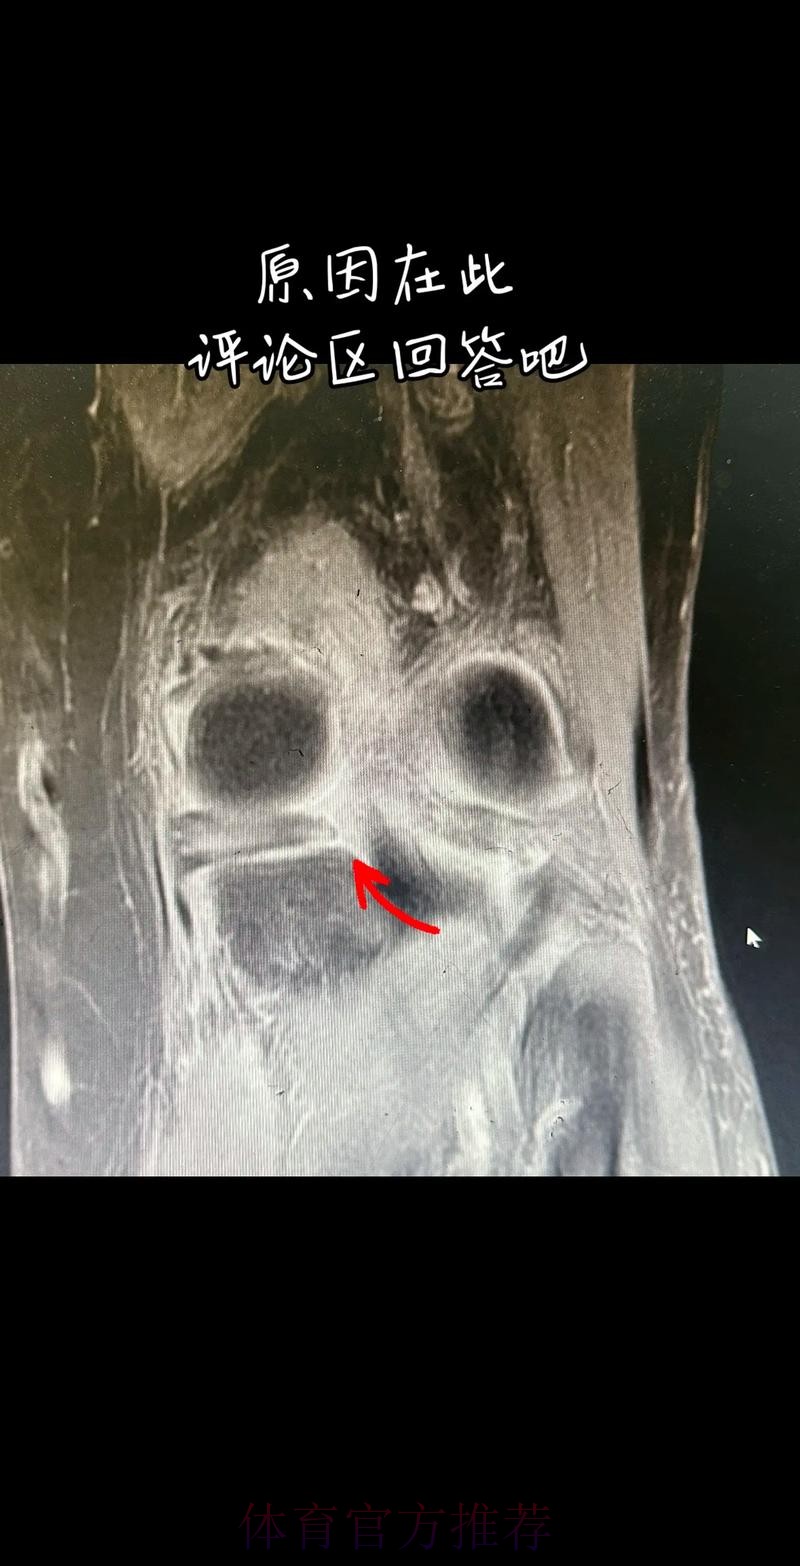

从医学角度看 半月板是膝关节内一块呈“C”形的软骨结构 其作用是缓冲冲击 稳定膝关节 并帮助分散压力 “左膝内侧半月板撕裂”通常说明在一次急停 旋转 或对抗中 半月板受到了超过其承受极限的力导致结构损伤 这类伤病常见于足球 篮球等需要频繁变向和对抗的项目 对于职业球员而言 半月板损伤严重程度不一 但共同点是都会影响支撑发力 跳跃以及变向时的稳定性 而官方给出的“预计伤缺6-8周”这个时间区间 往往对应的是中度损伤或通过微创手术加积极康复能够较快回归的情况 也意味着暂时没有出现必须长时间休战的最坏结果 表面上看 6-8周只是一个时间区间 但对顶级球队的赛程来说 这段时间可能包含多场联赛 甚至关键杯赛淘汰轮 相当于缺席一个赛季中最密集的一段周期 需要强调的是 这个“预计”并不是绝对数字 它取决于撕裂的位置 大小 修复方式 以及球员个体的恢复能力 有时若采取保守治疗 球员在6周时即可参与部分训练 但要达到比赛要求则可能接近8周甚至稍长 此外 精英运动员的康复不仅仅是伤口愈合 还包括力量恢复 协调重建 和心理自信的回归 阿拉巴要在有限时间内完成从“伤病患者”到“可靠首发”的角色转换 这一过程复杂程度远远超出一纸通告所能呈现